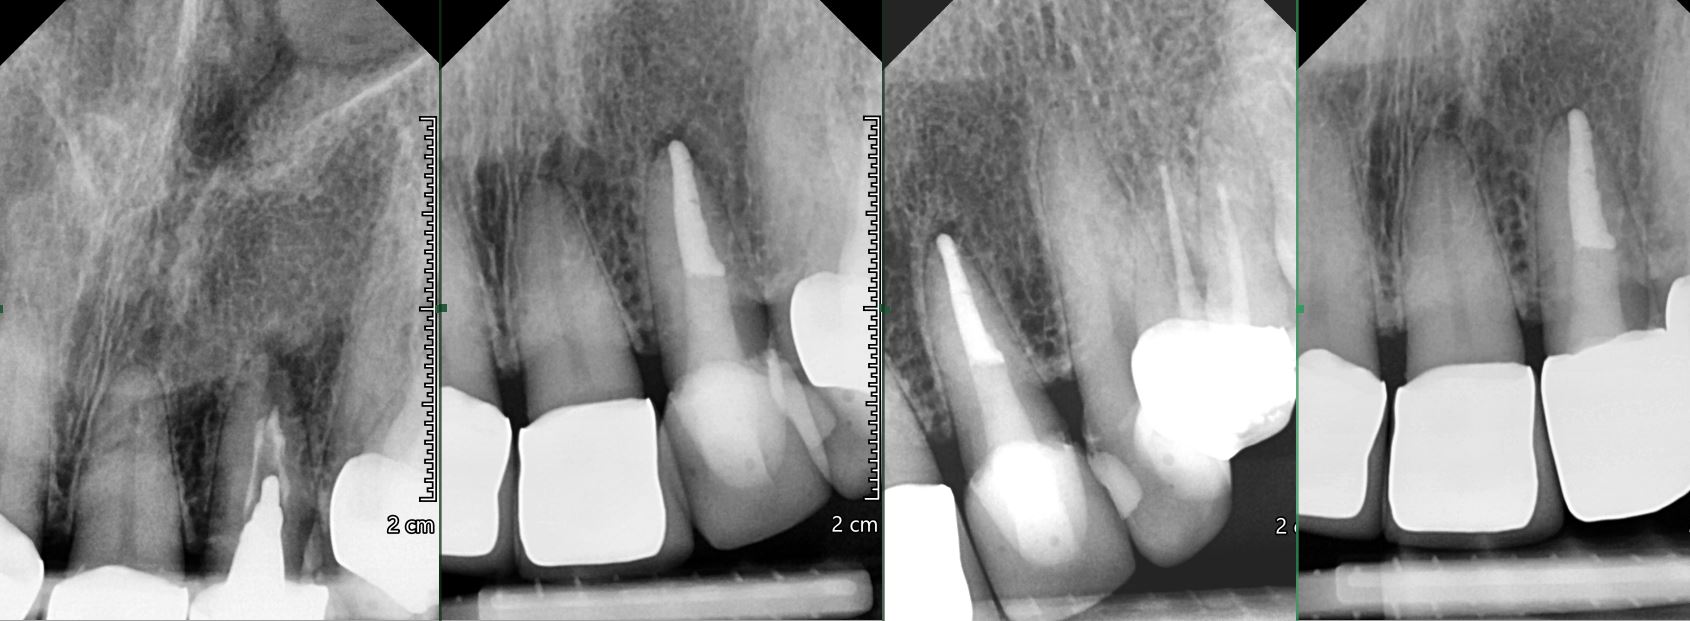

OŠETŘENÍ PACIENTŮ POD OPERAČNÍM MIKROSKOPEM

Nabízíme možnost delegovat Vaše pacienty k (re)endodontickému ošetření pod operačním mikroskopem.